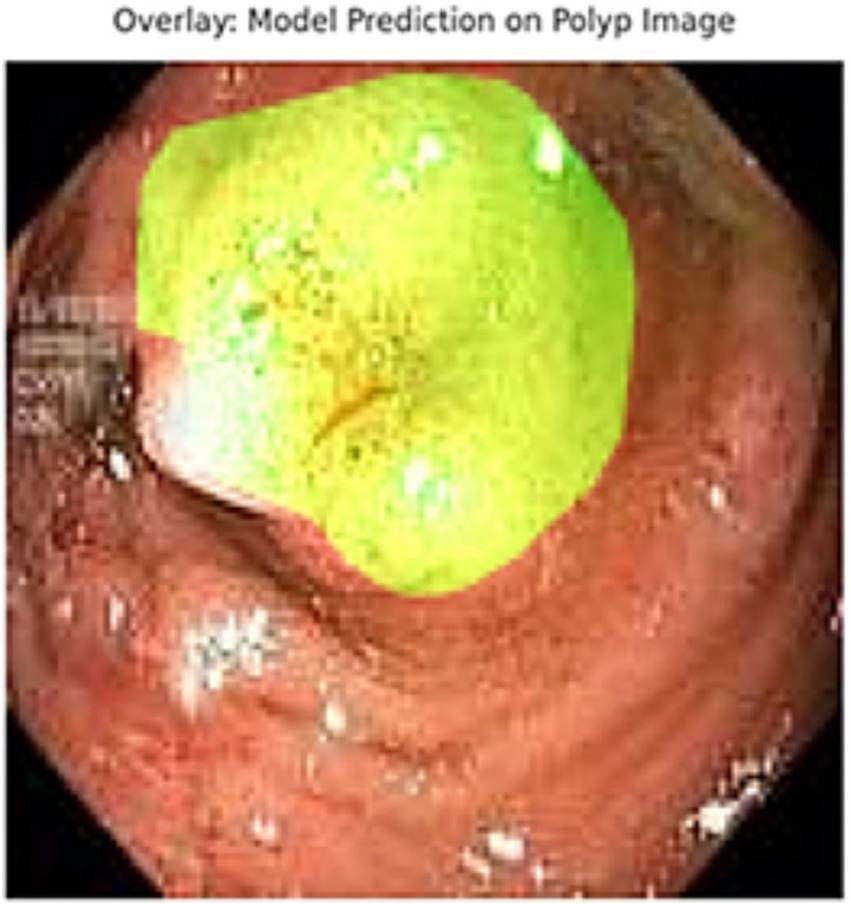

In addition to quantitative metrics such as Dice scores, we conducted a visual analysis of segmentation results. Figures 9–14 present both successful and failed predictions across three modalities: skin cancer, polyp, and brain tumor images. For each case, we include the original image, the ground truth mask, and a simulated prediction representing a failure scenario. In the overlay images, the predicted mask is superimposed in green over the input image to visually evaluate alignment. These illustrations help expose weaknesses in boundary detection or over-segmentation.

Figure 13

Failed segmentation example on a polyp image. The predicted mask shifts to the right and misses part of the lesion.

Figure 14

Overlay visualization – polyp. Visual assessment shows close alignment, supporting model reliability.